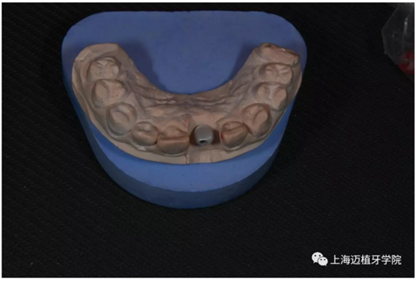

取工作模型

非工作模型

氧化鋯個(gè)性基臺(tái)